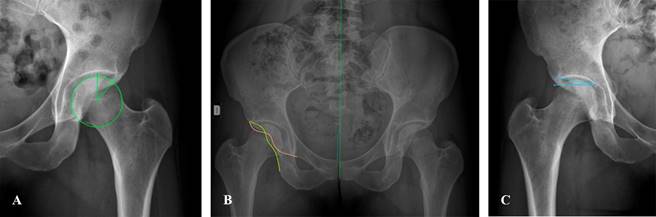

Signo de Trendelenburg: se solicita al paciente el apoyo monopodal en cadera afectada; si ésta se balancea hacia el lado afectado, es indicativo de debilidad de glúteo medio (Figura 2).

Figura 2: A) Evaluación de simetría de extremidades inferiores. B) Competencia de glúteo medio para estabilidad pélvica en plano horizontal. C) signo de Trendelenburg positivo izquierdo, que indica insuficiencia de glúteo medio izquierdo.

Las que nosotros recomendamos de manera sistemática son proyecciones anteroposterior en bipedestación, de Lequesne, Dunn a 45o y eje mecánico bipodálico. Con estas proyecciones podemos evaluar a la articulación coxofemoral en los tres planos anatómicos, es decir, en coronal, axial y sagital, brindándonos una perspectiva tridimensional de la articulación. Con el eje mecánico bipodálico, podemos evaluar las articulaciones de la rodilla y tobillo; asimismo, conocer la distribución de cargas, discrepancias y su impacto en la articulación coxofemoral (Figura 8).

Figura 8: A y B) Radiografía anteroposterior en bipedestación de pelvis. C) Proyección de Dunn a 45o. D) proyección a 90o. E) Proyección de Lequesne de cadera derecha o falso perfil.

La evaluación inicial por imagen debe incluir radiografía anteroposterior (AP) con apoyo y el falso perfil, el resto de las proyecciones específicas se solicitan de acuerdo con nuestra sospecha diagnóstica.

Para evaluar una radiografía AP adecuada tomamos como referencia la alineación de la sínfisis del pubis y coxis en el mismo plano y con una distancia entre ambos de 1-3 cm, simetría en ambos agujeros obturadores, crestas ilíacas y de ambos trocánteres menores, que son indicativos de correcta rotación interna de 15 a 20o, para evaluar de manera correcta en ángulo cérvico-diafisario de la cadera.

En la radiografía anteroposterior verdadera, podemos evaluar las distintas estructuras anatómicas, iniciando por las líneas acetabulares, la línea ilioisquiática, iliopectínea, las paredes acetabulares, en las que podemos identificar múltiples patologías como versiones, o bien datos o signos sugestivos de pinzamiento como el signo de crossover (Figura 9), donde la pared anterior y posterior se interceptan formando un «ocho». La sobrecobertura global se puede identificar con la relación de la línea iliopectínea y la escotadura acetabular (lágrima de Kohler), en donde la fosa debe ser lateral a esta línea; de no serlo, estamos ante una sobrecobertura femoroacetabular.7

Mediciones especiales

En esta proyección podemos valorar el ángulo Wiberg o centro borde (Figura 9A), indicativo de cobertura lateral, el cual se traza del centro de rotación de la cadera y la porción más lateral del acetábulo, cuyo valor normal es de 25 a 40o.

Otro ángulo de importancia para la sobrecobertura o descobertura acetabular es el índice acetabular o de Tönnis cuyo valor normal lo encontramos en 0 a 10o (Figura 9C).

Ángulo cervicodiafisario: cuyo valor normal es de 135-145o; > 145o se considera coxa valga, < de 135o coxa vara.

Ángulo de Sharp: formada por una línea inferior a ambas lagrimas acetabulares y línea que pasa por el extremo del borde acetabular lateral, determina la inclinación acetabular, cuyo valor normal es 40-45o.7

Índice acetabular de profundidad: se determina a través de una línea que une la porción superolateral e inferomedial del acetábulo entre la profundidad del mismo determinada por una línea perpendicular a la anterior en su porción media hasta el fondo acetabular, multiplicado el mismo por 1,000.2

Las proyecciones de Dunn a 45o y 90o de flexión, rotación externa de 45o y abducción de 20o son proyecciones específicas para valorar la esfericidad de cabeza femoral (importante para valoración de pinzamientos sobre todo tipo cam) y la unión craneocervical (Figura 10).7

Figura 10: Proyección de Dunn a 45o, medición de unión craneocervical, identificándose datos de pinzamiento tipo cam.

La radiografía de lateral o falso perfil de Lequesne, es de utilidad en la valoración de la morfología anterior de la cabeza femoral y su cobertura acetabular en la que se puede valorar el ángulo center edge de Lequesne y nos permite valorar la cobertura acetabular anterior, cuyo valor normal es de 25 a 35o (Figura 11).2

Figura 11: Proyección de Lequesne donde se puede valorar los cambios morfológicos de cabeza femoral y acetábulo en cadera derecha con sobrecobertura anterior del techo acetabular.